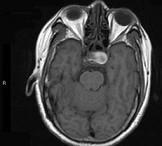

问题 男性,55岁,头痛一年余,两个小时前突然出现剧烈头痛,MRI检查如图所示,最可能的诊断为 ( )

选项 A、垂体瘤并卒中 B、动脉瘤 C、脑膜瘤 D、颅咽管瘤 E、垂体瘤

答案 A